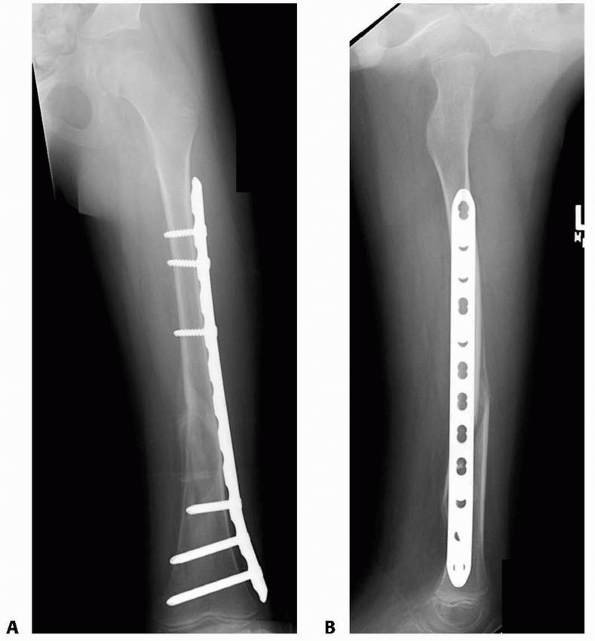

according to the specifics of the implant chosen. In general, the

smallest rod that maintains contact with the femoral cortices is used

(generally 9 mm or less) and is locked proximally and distally (Fig. 22-23). Only one distal locking screw is necessary, but two can be used.112

Rods that have an expanded proximal cross-section should be avoided,

because they require excessive removal of bone from the child’s